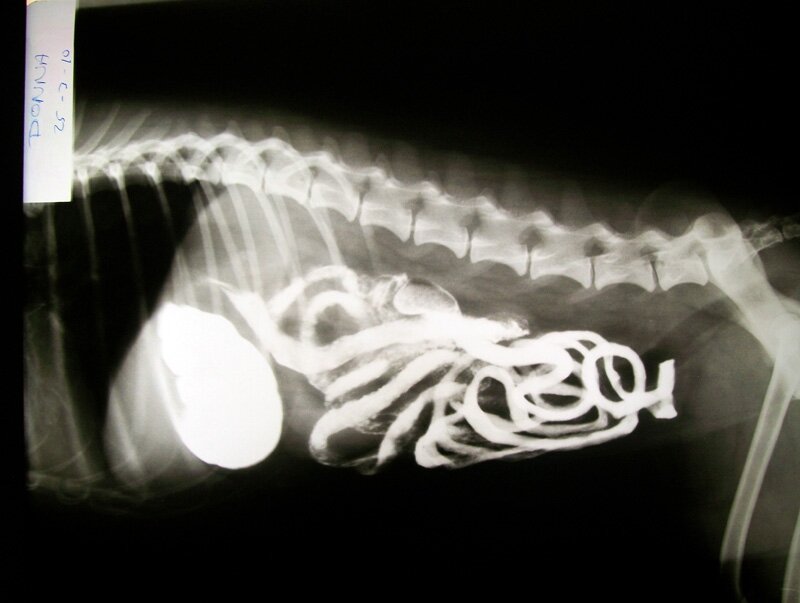

La clínica cuenta para ello con aparatos de ecografía abdominal y ecocardiografía doppler, electrocardiógrafo, radiografía de alta frecuencia, oftalmoscopia directa y un completo laboratorio.